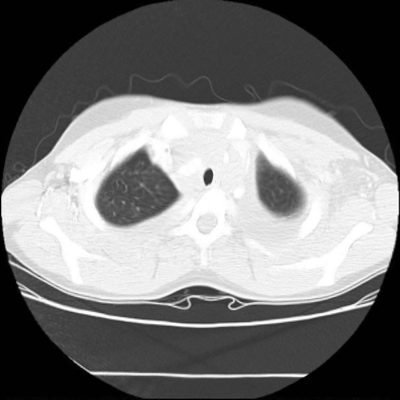

7.3. Real CT images

We now consider applying the proposed image registration method on real lung CT images retrieved from the National Lung Screening Trial (NLST) dataset [1]. Fig. 9(a) and Fig. 9(b) show two slices of lung CT images that we use as the source and the target (see Fig. 9(c) for the absolute intensity difference). We remark that the CT images are originally with different intensity, and so we apply an intensity histogram matching before running the registration experiment. Fig. 9(d) shows the registration result obtained by our proposed method. It can be observed that our method successfully produces a large deformation on the right lung of the source image to match that of the target image (see also Fig. 9(e) for the final absolute intensity difference). On the contrary, DDemons [47] (Fig. 9(f)), LDDMM [5] (Fig. 9(g)), Elastix [29] (Fig. 9(h)) and DROP [18] (Fig. 9(i)) all fail to produce an accurate and bijective registration result. This shows that our method is more capable of handling large deformation image registration.

We then test our method on slices of chest CT images obtained from the Open Access Biomedical Image Search Engine [2]. Fig. 10(a) and 10(b) show the source image and target image respectively, and the intensity difference is shown in Fig. 10(c). The registration result obtained by our proposed method is shown in Fig. 10(d) (see also the result with the deformed underlying grid in Fig. 10(e)). From the final intensity difference plot in Fig. 10(f), it is easily to see that our method matches not only the two large components but also the small dot at the center very well. On the contrary, DDemons [47] produces a suboptimal registration result with a significantly larger mismatch of the small component at the center (see Fig. 10(g) and Fig. 10(h)).